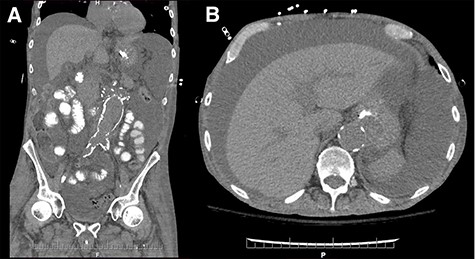

On postoperative Day 5, diet was resumed and the patient subsequently developed abdominal distention, for which a computer tomography scan was performed (Fig. 1a and b). Therapeutic paracenteses confirmed chylous ascites and he was placed on total parenteral nutrition (TPN) and octreotide. Despite conservative management, the ascites re-accumulated on resumption of oral intake.

Coronal (A) and axial (B) sections of non-contrast enhanced abdominal computed tomography showing accumulation of large volume of peritoneal fluid. Aortic graft appears intact.